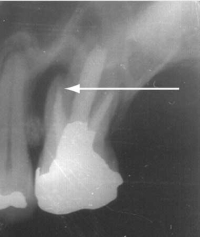

Segment of an orthopantomogram showing an impacted wisdom tooth: a radiolucent area (arrow) is seen behind an impacted right lower wisdom tooth from a patient with pericoronitis.

A 35-year-old man presented to a hospital emergency department with severe pain of 2 days’ duration originating in the left lower jaw and radiating into the temporal area. The pain was described as sharp and shooting in nature; it was present all the time and not relieved by paracetamol + codeine. Complete general and local physical examination performed at the emergency department did not reveal any obvious cause of the pain. A diagnosis of trigeminal neuralgia was made by exclusion, and the patient was prescribed 200 mg carbamazepine twice a day and advised to consult his GP during the week. The patient presented 32 hours later complaining of excruciating pain, despite having taken three carbamazepine tablets.

On examination of the oral cavity, a partially erupted left lower molar was noted, with surrounding mucosal erythema and extreme tenderness of the surrounding gum (see image in this Box). A diagnosis of pericoronitis was made.

Ideal management: Pericoronitis should be treated by irrigation of the pericoronal space with a sterile solution such as saline or 0.12% chlorhexidine. Broad spectrum antibiotics should be given if there are systemic symptoms.7,8 The patient should be referred to an oral and maxillofacial surgeon/dentist for surgical extraction of the tooth.